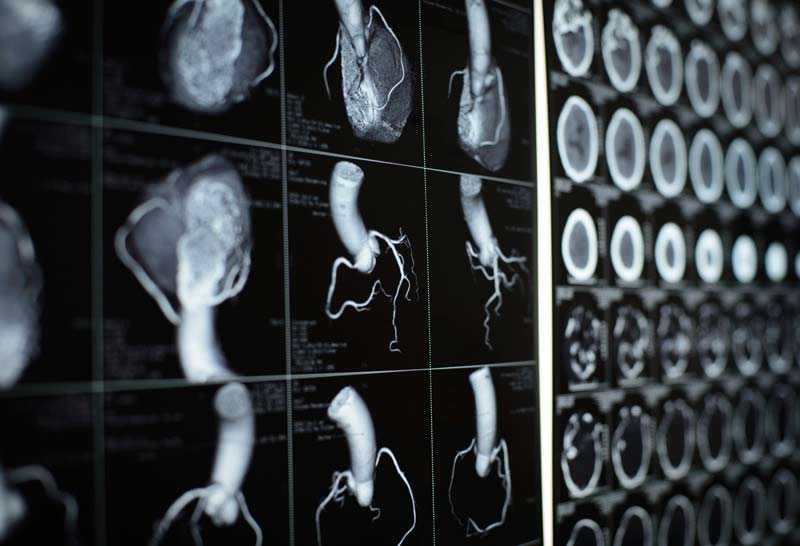

Комп'ютерна томографія (КТ) серця та коронарних артерій – це неінвазивний метод обстеження, що дозволяє візуалізувати вінцеві артерії, оцінюючи їх прохідність, ступінь звуження та анатомічні особливості. КТ використовує рентгенівські промені для створення високоточних тривимірних зображень артерій, що постачають серце кров'ю, а також інших структур серця. Це дослідження дає можливість оцінити стан артерій, міокарда, клапанного апарату та інших важливих компонентів серця.

КТ серця дозволяє лікарям оцінити стан коронарних артерій, виявляючи звуження та атеросклеротичні бляшки, які можуть ускладнювати кровопостачання серця. Також метод використовується для оцінки клапанного апарату, порожнин серця та легеневих судин. КТ може показати:

КТ серця має значні можливості в оцінці стану серцево-судинної системи. Воно дозволяє отримати детальні зображення артерій та серцевих структур, визначити ступінь звуження судин та оцінити їх функціональний стан. Основні можливості КТ серця:

- отримання високоточного зображення коронарних артерій;

- можливість тривимірної реконструкції артерій;

- використання контрастної речовини для покращення візуалізації.